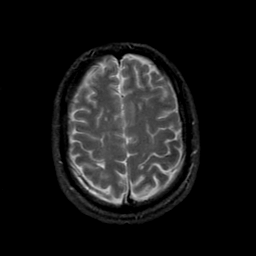

MR Study #21, November 3, 1991 -- Slice #39

[Home][Help][Clinical][Tour 1][Tour 2] Slice 39